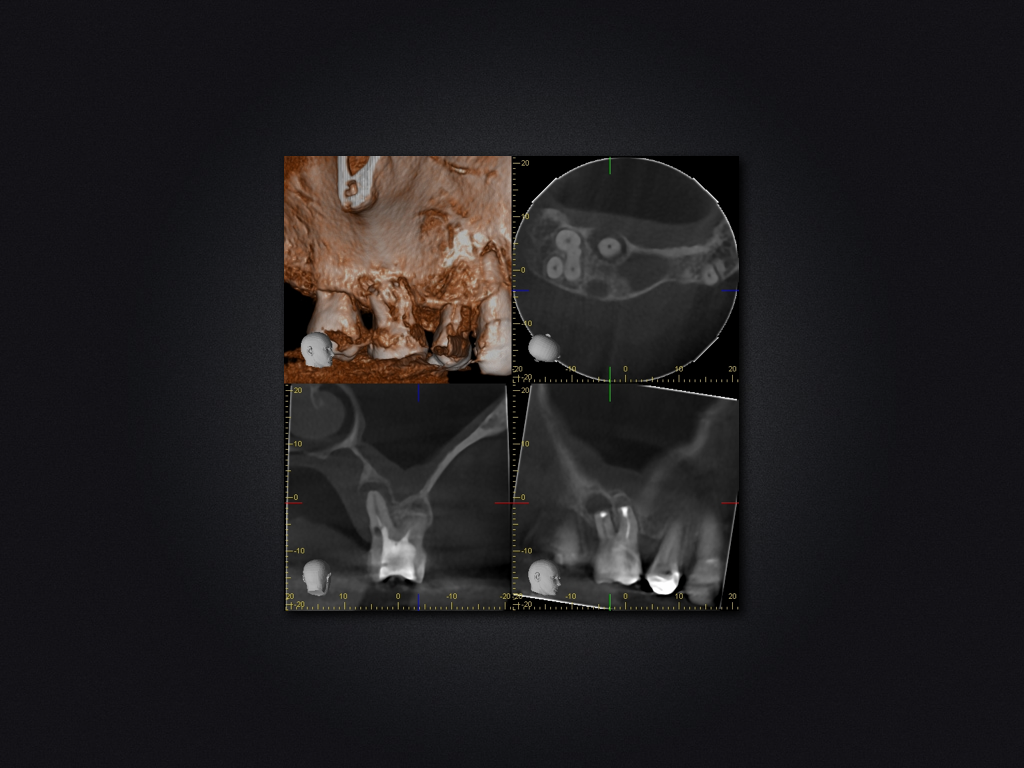

16D.004

Saving Hopeless Teeth (XXX)